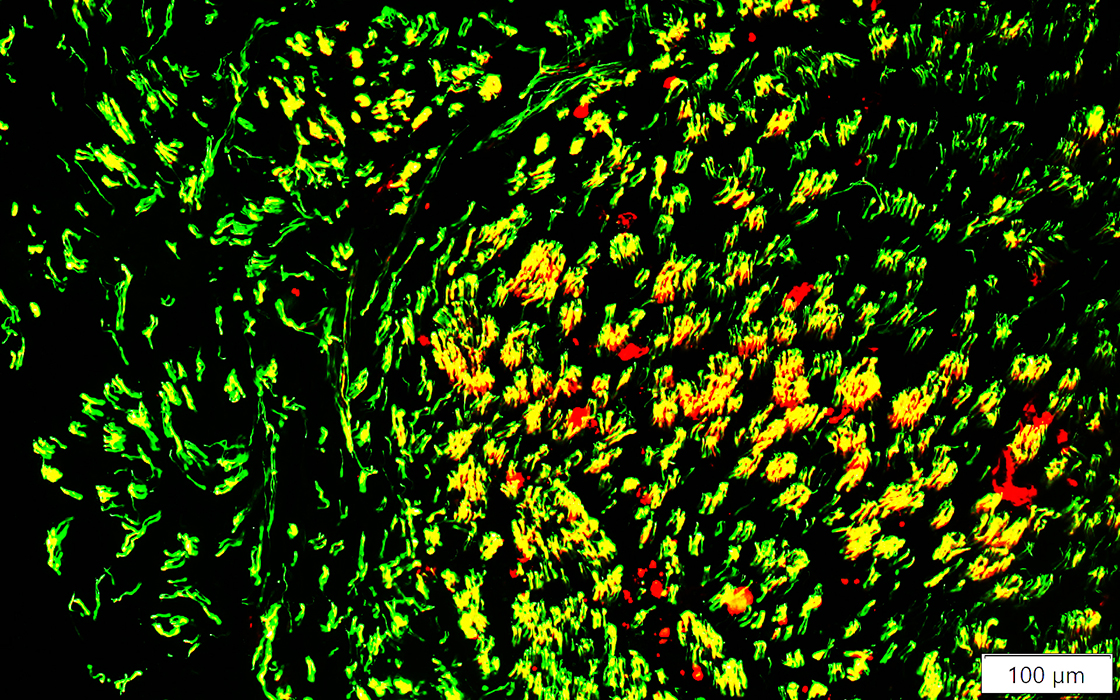

Neurofilament (Green); NCAM (Red)

NCAM

Present in Schwann cells around most axons in Neuroma (Left) & surrounding axon sprouts (Right)

Neurofilament (Green); MBP (Red)

|

Immature Schwann Cells/Myelin: Express MBP in cells on axons with thin, or no, myelin

Small & Intermediate-sized axons

Many have associated MBP+ Schwann cells (Yellow)